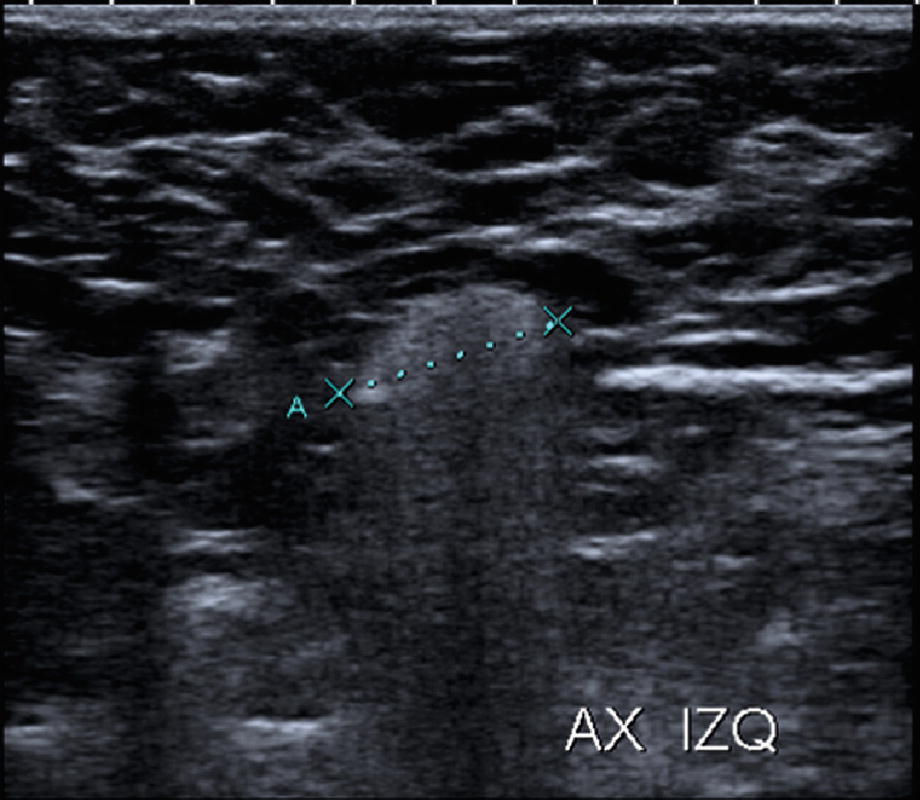

Ultrasound of the axillary region. Note the left axillary echogenic appearance with loss of the normal cortico-hilar relationship and later “snowstorm” sign, produced by the migration of silicone

The ultrasound scan must necessarily extend beyond the limits of the breast to include the thoracic wall and the axilla, due to the ability of silicone to migrate frequently to these locations. The sonographic findings there will be similar to the previously described “snowstorm.” [16]